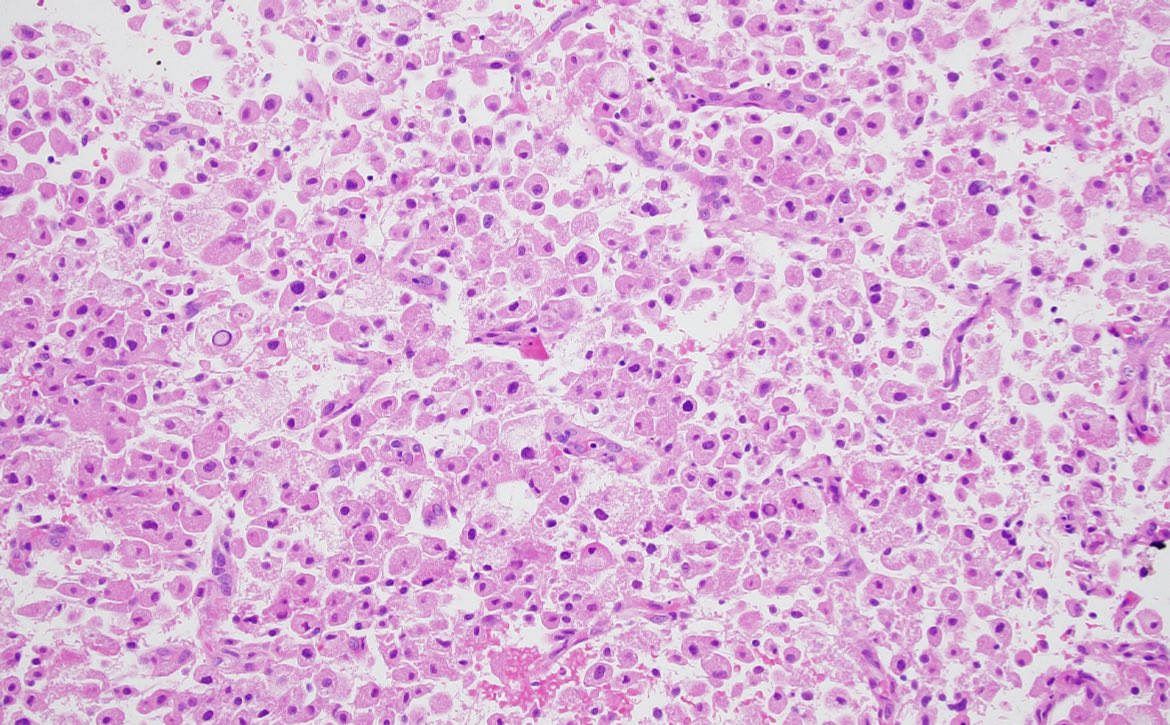

3 years

60s yo with brain mass. H&E and GFAP shown. Differential? Additional studies? Or are you brave enough to make a diagnosis? #neuropath #PathTwitter 🧠🔬

13

33

86